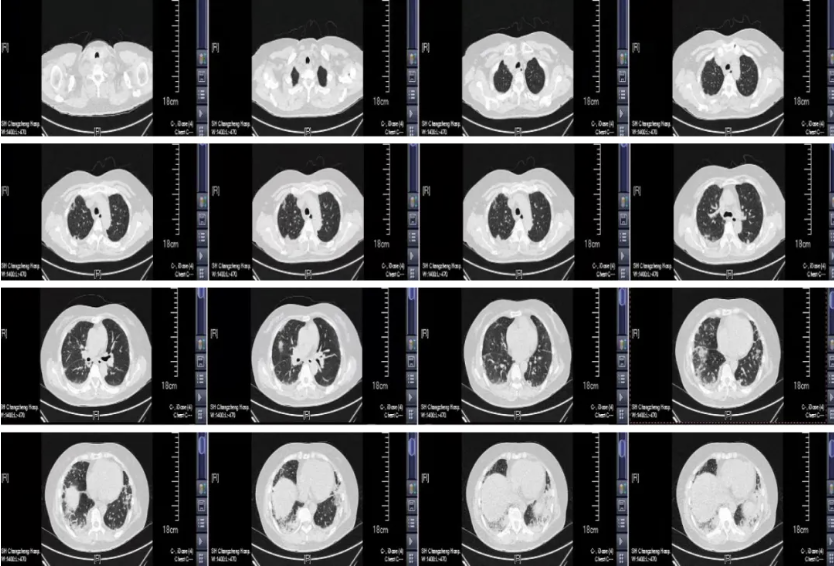

图:(从左至右)9-24、10-7、10-14、10-23、10-27

但很快患者的病情升级,影像学进展,氧和指数持续降低。入院后完善检查,患者血气分析提示低氧血症,复查胸部CT见双肺胸膜下病变范围进一步增大,部分呈间质样改变,结合患者“皮疹+肌损害+间质性肺病”的疾病模式,我们仍然考虑CTD-ILD,重点考虑肌炎相关的间质性肺炎,为进一步明确诊断,予外送肌炎特异性抗体谱25项抗体检测,在等待结果汇报的过程中患者干咳气喘症状逐渐加重,血气分析提示氧和指数逐渐降低。

抗MDA5抗体阳性皮肌炎相关ILD可能在HRCT上表现为严重的OP,直接导致弥漫性肺泡损伤,而无慢性肺部改变。下肺外侧带或沿支气管血管束分布的实变或磨玻璃影(ground glass opacities, GGO)是抗MDA5抗体阳性皮肌炎HRCT上的特征性表现,且与短期预后相关。通过动态监测HRCT的变化,对抗MDA5抗体阳性皮肌炎出现RP-ILD的早期诊断具有重要价值。HRCT显示进展为RP-ILD的特征性表现为在短期内从胸膜下或(和)小叶周围斑片状影迅速进展为广泛的实变影。